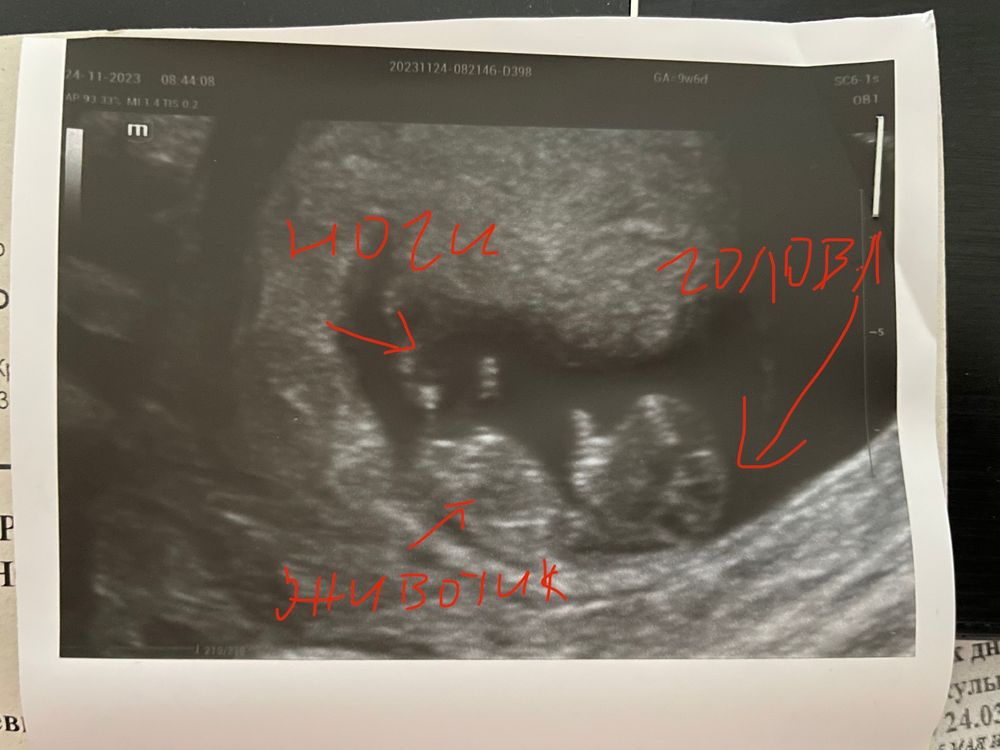

так вот, была вчера на УЗИ, фото прикладываю. ☺️ Врач сказала, что все хорошо, развиваемся по сроку (только плодное яйцо у меня почему-то аж на 11 н 2 дня 🤨 а у меня 10 только сегодня.

мелкий там двигается во всю, сердечко тарахтит ритмично ☺️